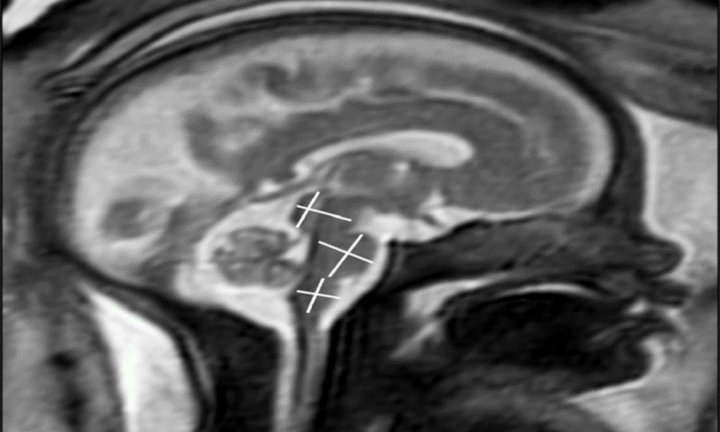

Mắc COVID-19 trong thai kỳ có ảnh hưởng tới não của thai nhi?

Nhiều phụ nữ bị nhiễm virus SARS-CoV-2 khi mang thai lo ngại virus có thể ảnh hưởng đến não của thai nhi.